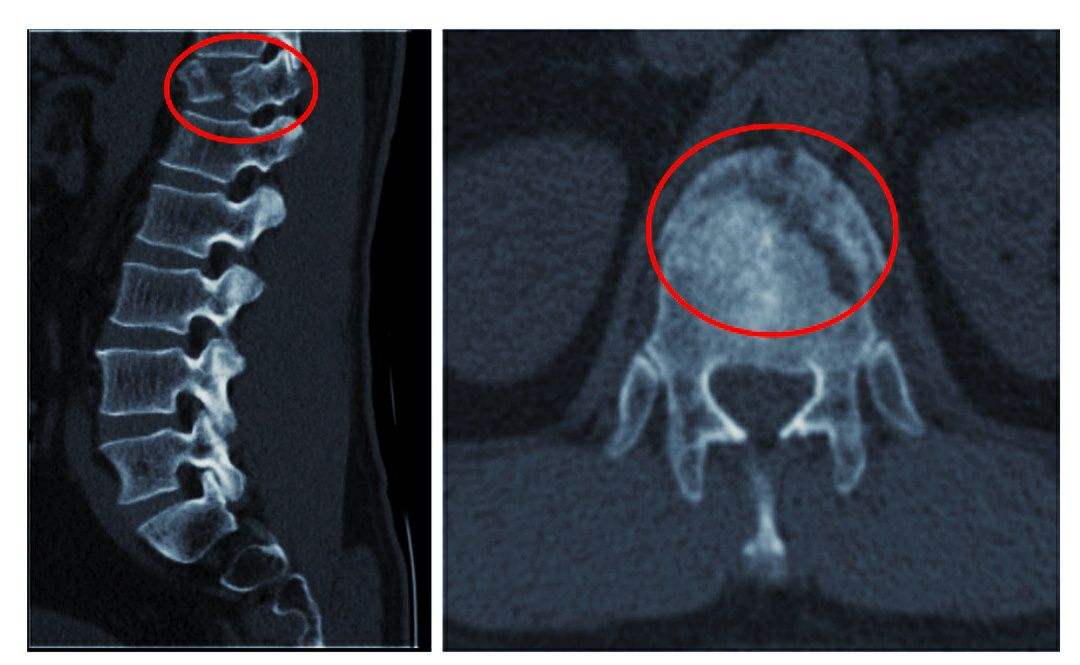

2、椎體緣、關(guān)節(jié)突、鉤椎關(guān)節(jié)骨贅形成

骨贅即骨質(zhì)增生俗稱為骨刺,是指骨關(guān)節(jié)邊緣上由于長期慢性損傷引起瘢痕組織增生,天長日久可產(chǎn)生鈣質(zhì)沉著變成骨質(zhì)而形成的。

由于椎間盤的退變,其后果必然導(dǎo)致頸椎生理曲線的改變,破壞了椎體間的平衡。久之,機(jī)體為了抵抗疼痛,使神經(jīng)免受刺激,建立新的平衡,而產(chǎn)生代償性骨贅,來穩(wěn)定脊柱。當(dāng)然骨贅形成的主要原因是急慢性損傷,骨贅的形態(tài)及部位與損傷的性質(zhì)等有關(guān),骨贅的大小與年齡有關(guān),與癥狀的輕重不一定成正比。若骨贅發(fā)生于椎間孔或椎管附近,可產(chǎn)生神經(jīng)根、椎動(dòng)脈或脊髓受壓癥狀。